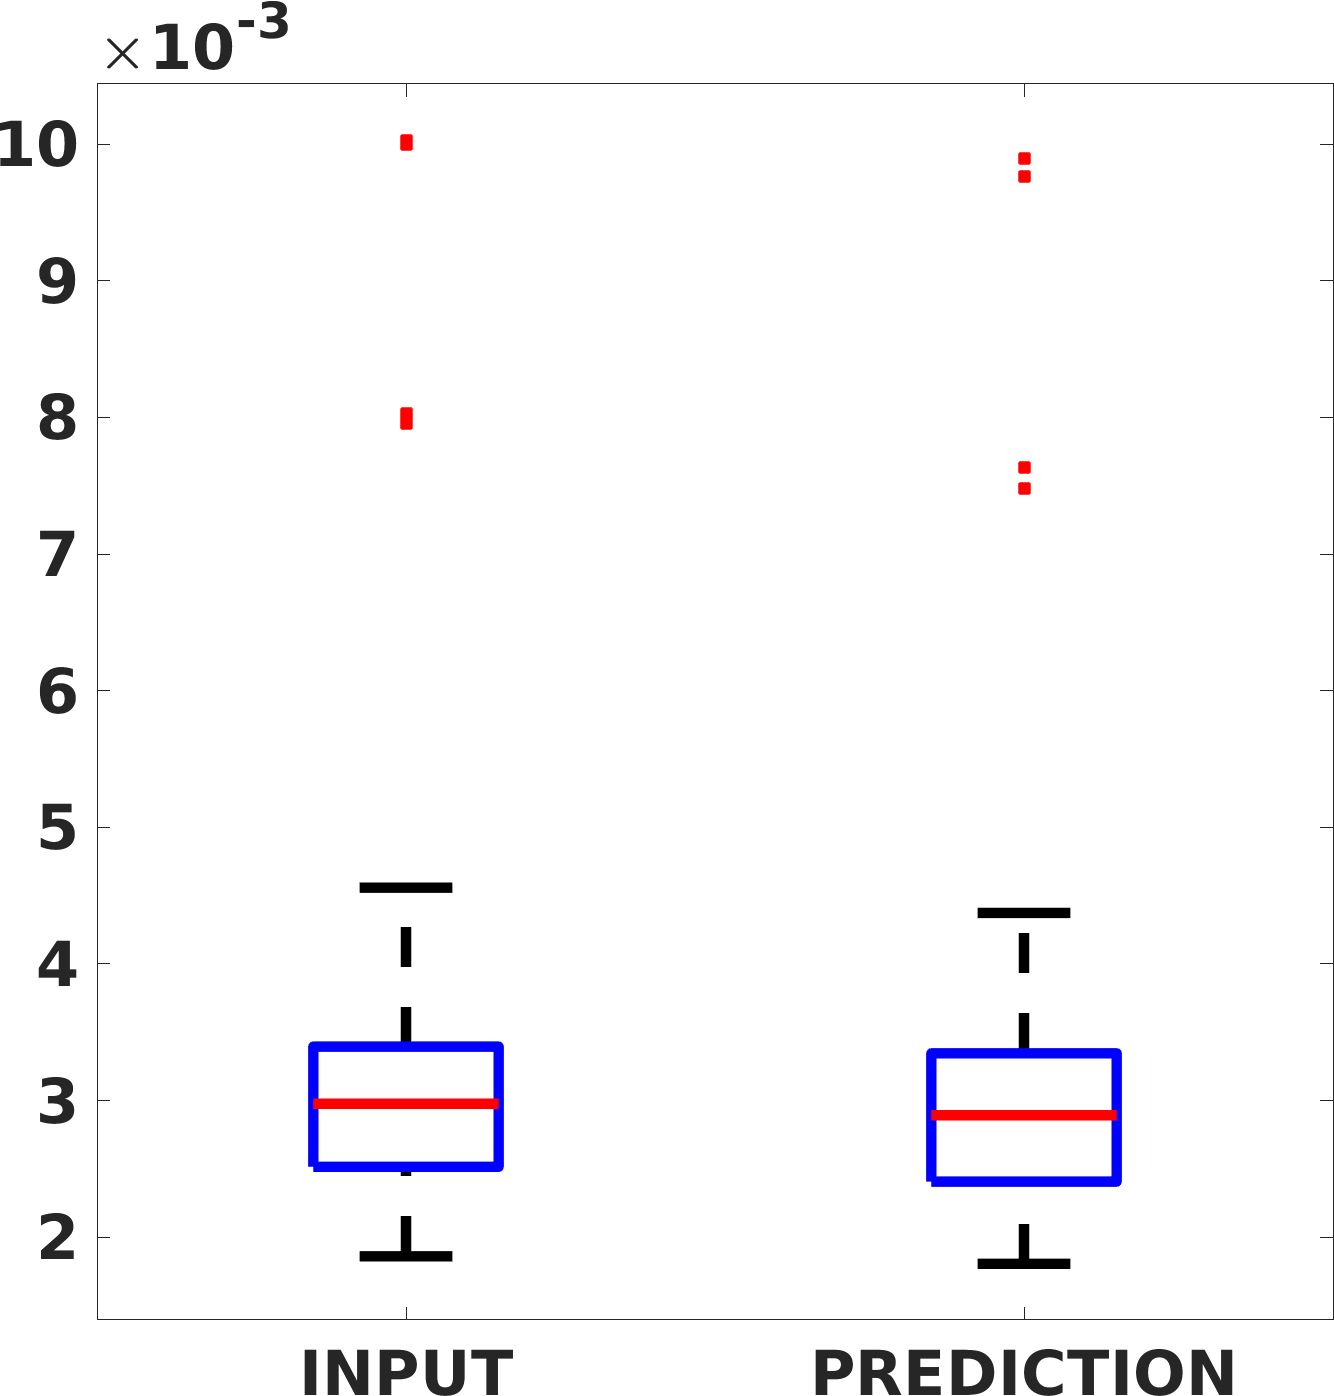

Fig. 7(a-b-c, left) shows the box plot of the statistics of the PSNR on three different anatomical districts, comparing the target images with the prediction and the cubic convolution, respectively. The metrics are computed on a data set of 200 images of the same district and with the same up-sampling factor. We report that the PSNR median value improves of on obstetric 2X raw images, on cardiac 2X raw images, and on abdominal raw 4X images.

Fig. 7(a-b-c, right) shows the histogram of the absolute value of the error with respect to the target image, of the prediction and Cubic convolution results, respectively. The histograms show the number of pixels where the prediction error is lower than 5 (i.e., the first bin of the histogram), which means very similar to the target when visually analysing the images. From the Cubic convolution to the predicted images, this value increases of on obstetric 4X raw images, on cardiac 4X raw images, and on abdominal 4X raw images.

Fig. 8 shows the box plot of the SSIM (a-b-c, left) and MAE (a-b-c, right) quantitative metrics, as performed for PSNR metric. Also, these metrics show that our method improves the results of Cubic convolution both in terms of average value and variability. For example, the SSIM median value improves of on obstetric 4X images and the MAE median value improves of on cardiac 2X images.

Fig. 17 (left) shows the box plot of the quantitative metrics, comparing the target images with the prediction and the Cubic convolution, respectively. The PSNR metric is computed on a data set of 200 images, belonging to the same district, and with the same up-sampling factor. Analysing the obstetric anatomical district and concerning the corresponding raw images (Fig. 7 (a, left)), the denoising allows the network to significantly improve the results of the up-sampling and the prediction. In particular, comparing the target images with the predicted images, the median PSNR value of obstetric 2X denoised images is 51.8, compared to the median PSNR value of obstetric 2X raw images which is 36.9.

Fig. 17 (right) shows the histogram of the absolute value of the error with respect to the target, of the prediction and Cubic convolution respectively. This result shows that our framework increase of and (2X and 4X, respectively) the number of pixels where the prediction error is lower than 5, which is very similar to the target when visually analysing the images, and improved with respect to the learning framework applied to raw images. According to Fig. 18, our method improves the accuracy of Cubic convolution. For example, the SSIM increases of on cardiac 2X and the MAE increases of on abdominal 4X.